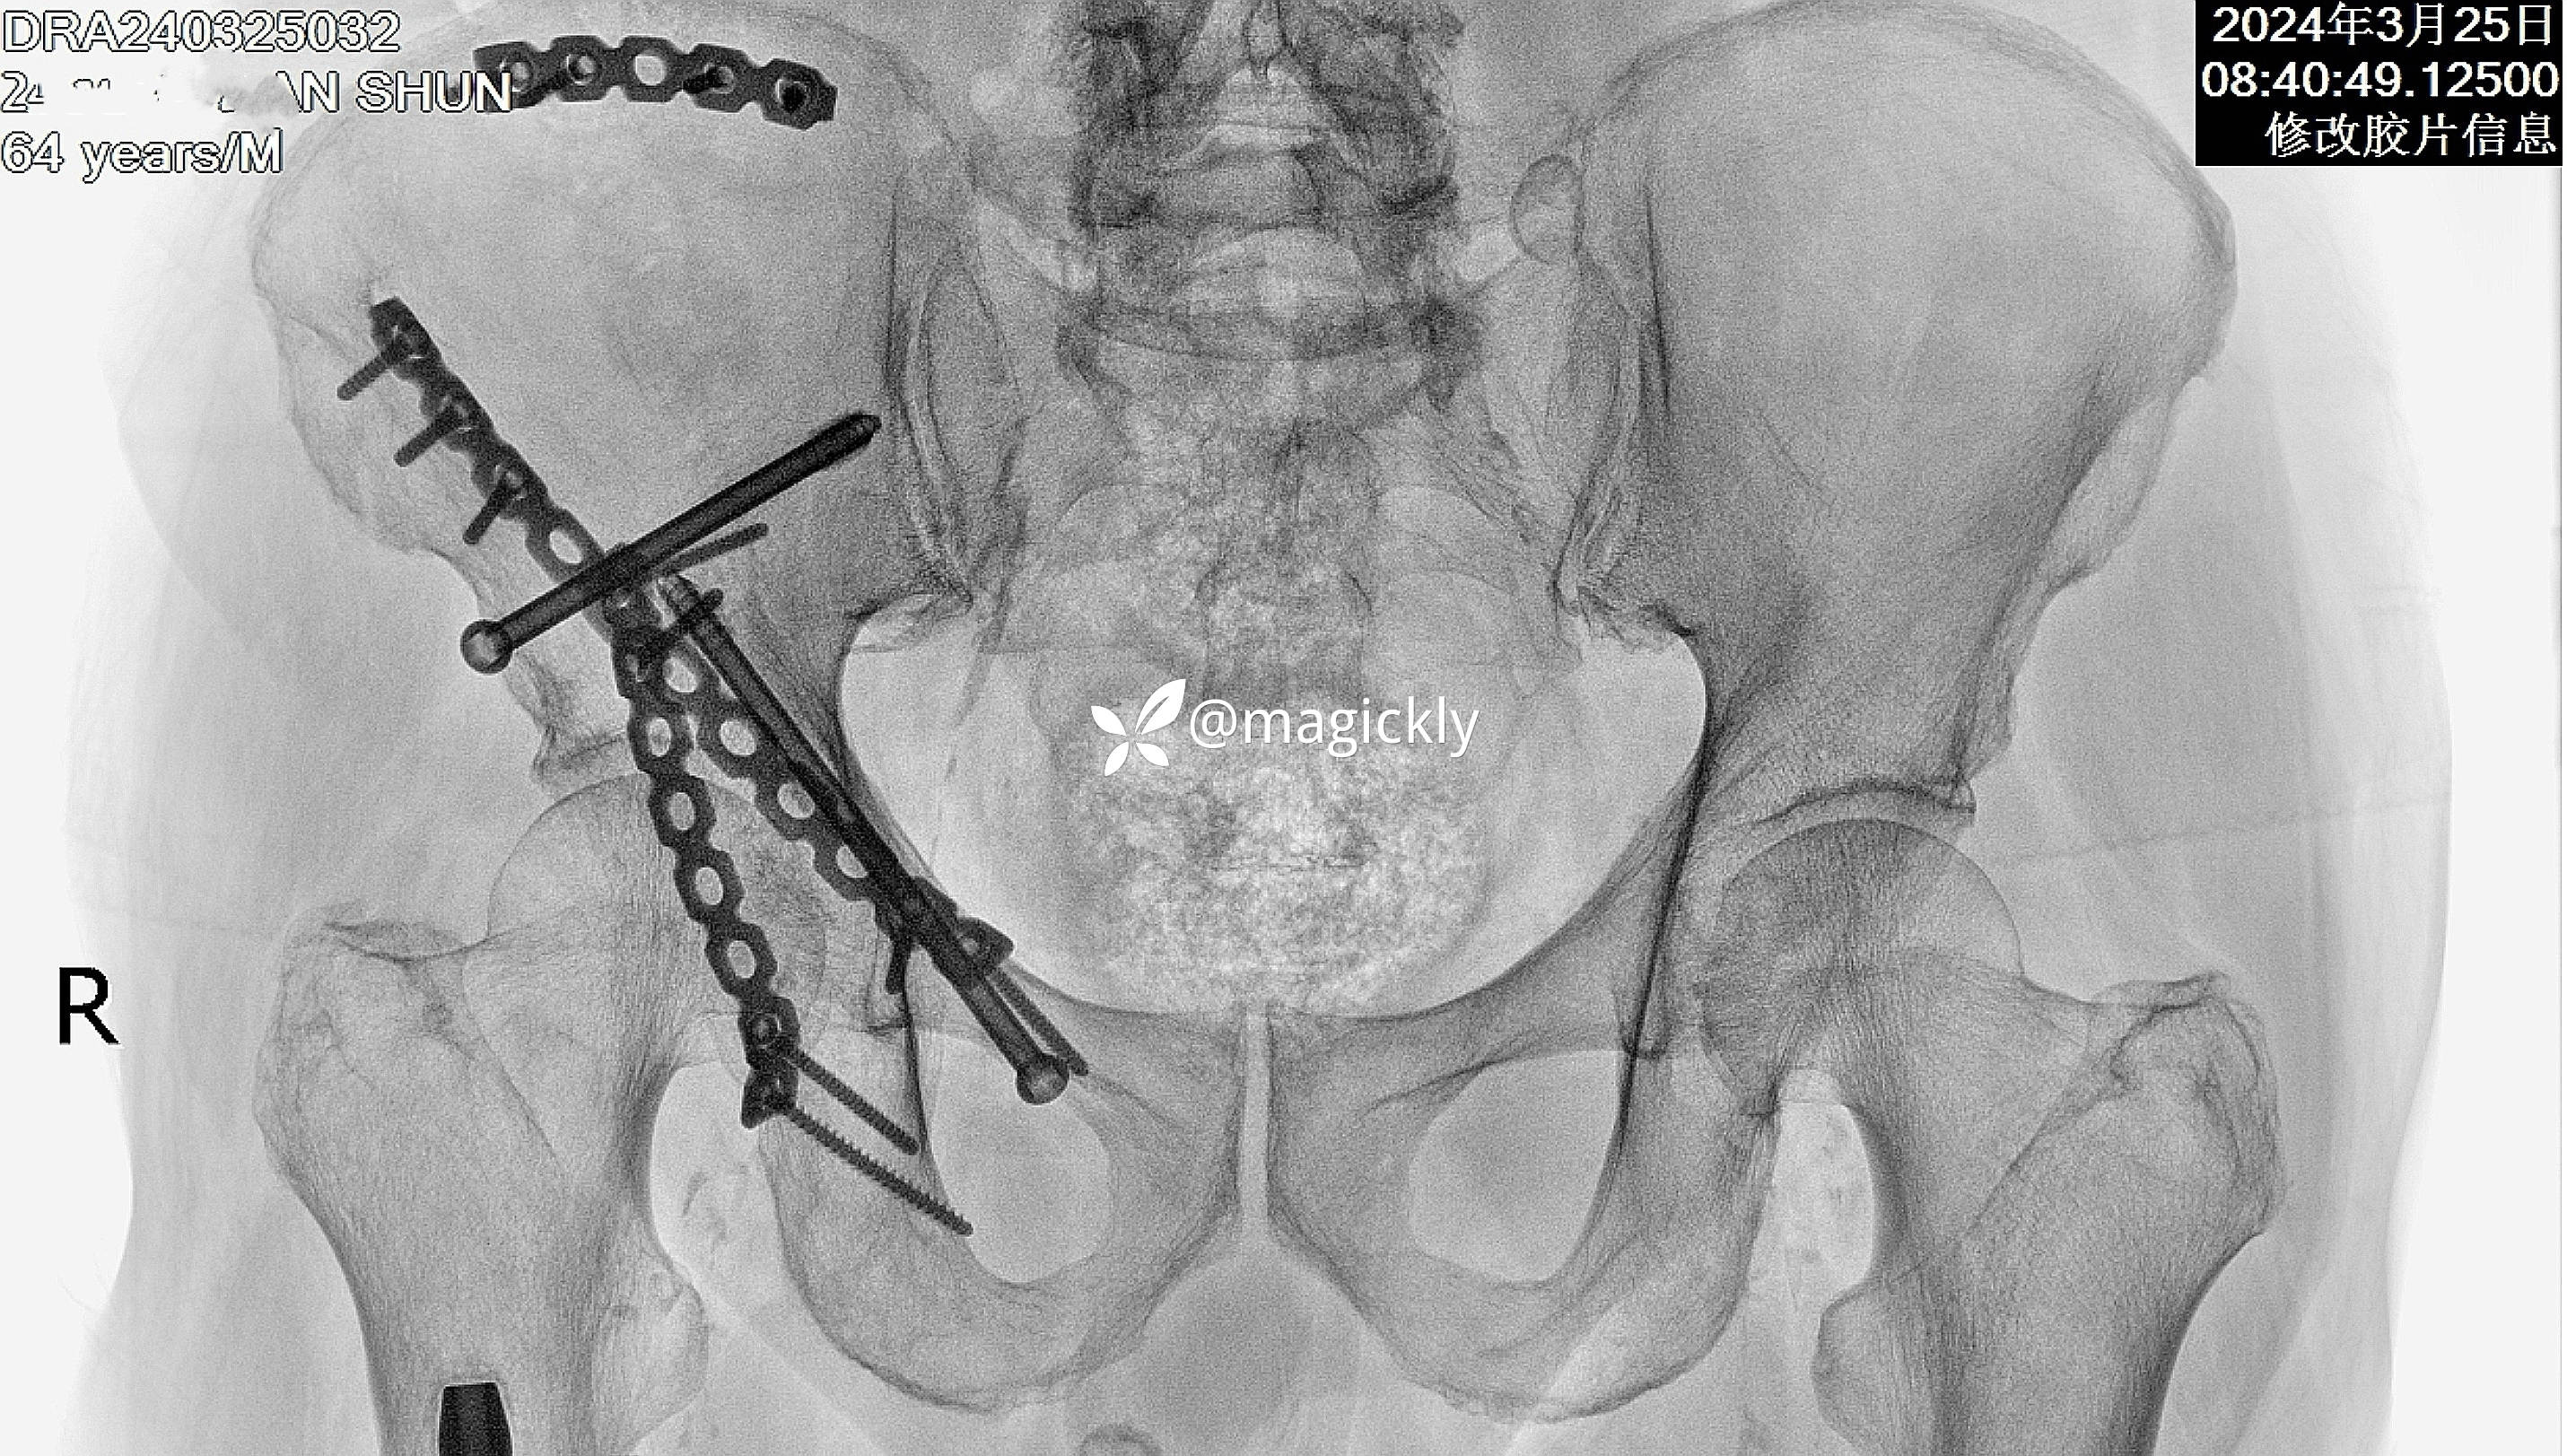

【患者信息】:男患,老年。

【主诉】:重物咋伤后右侧髋部疼痛、活动受限。

【检查】:局部体征明确,影像学结果如下

【临床诊断】:髋臼骨折(后上壁)